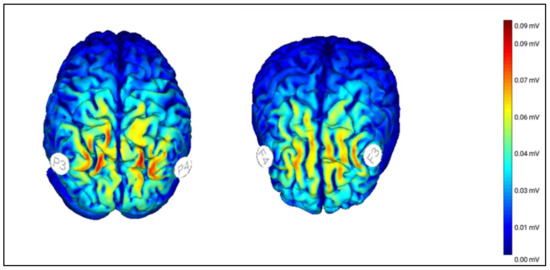

2.4.2. Transcranial Random Noise Stimulation